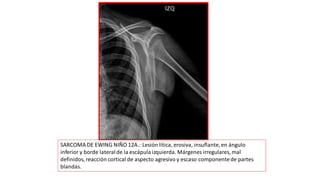

SARCOMA DE EWING NIÑO 12A.: Lesión lítica, erosiva, insuflante,en ángulo

inferior y borde lateralde la escápula izquierda. Márgenes irregulares, mal

definidos, reacción cortical de aspecto agresivo y escaso componentede partes

blandas.

SARCOMA DE EWINGNIÑO 12A.: Lesión lítica, erosiva, insuflante,en ángulo inferior y borde lateralde la escápula izquierda. Márgenes irregulares, mal definidos, reacción cortical de aspecto agresivo y escaso componentede partes blandas.